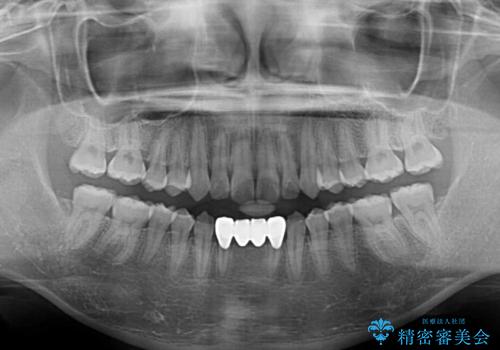

矯正治療終了後に速やかにオールセラミックブリッジを装着していくこととしました。

結婚式の予定があるとのことで、できる限り歯列を整え、挙式直前で残った乳歯を抜歯してブリッジの仮歯を装着するプランを立てたのですが、途中妊娠をされたため、麻酔をするタイミングを検討し、うまく前歯を整えることができました。